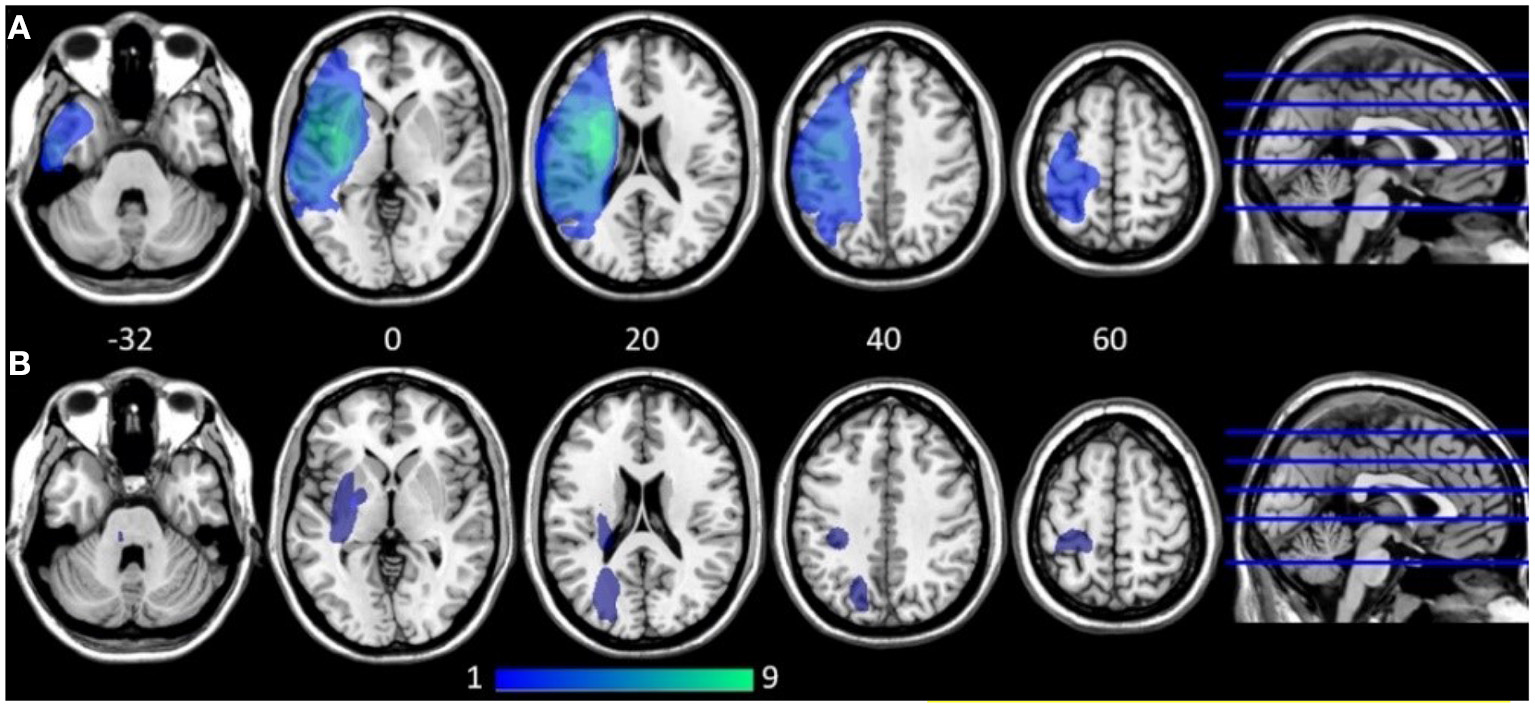

All participants with AOS, aphasia, and NVOA (hereafter called the AOS group) had a left MCA stroke with cortical lesions extending into subcortical white matter. The majority were caused by ischemic strokes; one participant had a hemorrhagic stroke. In the group without a speech-language impairment (No SLI group), the lesions were in general smaller and subcortically distributed (Figure 1). Two in this group had hemorrhagic strokes, whereas all others had ischemic strokes. A Mann-Whitney U test indicated that the lesion volume was significantly larger in the AOS group (Mdn = 121.9 cm3) than in the No SLI group (Mdn = 8.5 cm3), U = 2.0, p = 0.002 (Table 3). No significant correlation existed between lesion volume and any of the behavioral scores in the AOS group (at A1; ASRS rho = −0.35; A-ning rho = 0.18; BNT rho = 0.24; NVOA rho = −0.35). None of the participants in the No SLI group had a lesion overlap with any of the selected ROIs. In the AOS group, three (33%) of the participants had over 25% damage to the left vPMC, seven (78%) had over 25% damage to the left aINS, and seven (78%) to the left IFG. As shown in Table 4, several had over 25% damage to more than one ROI. There was no significant correlation between lesion volume and measures of FC in the selected network. A non-significant trend was found for the left aINS and left vPMC at the 6-months follow-up (rho = 0.65, p = 0.06).

Figure 1

Lesion overlap map at ≈ 4 weeks post stroke onset shown on five axial slices (z coordinates provided). Dark blue indicates low lesion overlap, light green indicates high overlap. (A) Participants with apraxia of speech, aphasia, and non-verbal oral apraxia (n = 9). (B) Participants with no speech-language impairment (n = 6). All participants with apraxia of speech, aphasia, and non-verbal oral apraxia had cortical lesions in the middle cerebral artery territory with extensions into deep subcortical white matter where the largest lesion overlap was found. SMA was not lesioned in any of the participants in the AOS group. The participants without speech-language impairment had in general smaller lesions spread in mainly subcortical areas.